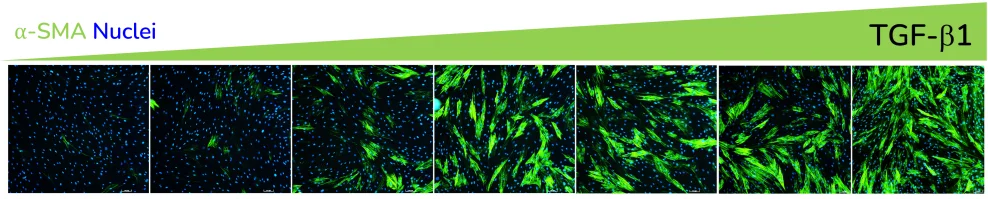

- Increased expression of α-SMA

α-SMA expression in response to dose-dependent treatment with TGF-β1. Images were acquired using the ImageXpress Confocal HT.ai imaging system. Image Credit: Newcells Biotech

- Increased α-SMA strand perimeter

TGF-β1 dose-dependently increases α-SMA strand perimeter indicating increased contractile potential of activated fibroblasts, while ALK5 inhibitor SB525334 shows a decreasing trend (A&B) Data for α-SMA strand perimeter from three healthy human lung fibroblast donors. Image Credit: Newcells Biotech

- Increased extracellular collagen I deposition

Extracellular collagen I deposition in response to dose-dependent treatment with TGF-β1. Images were acquired using the ImageXpress Confocal HT.ai imaging system. Image Credit: Newcells Biotech

Exposure to ALK5 inhibitors SB431542 and SB525334 reduces the effect of TGF-β1 at pathophysiologically relevant concentrations.